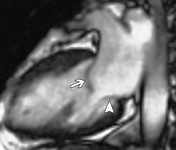

Mitralna insufincijencijaPrimarno ostecenje listica najcesce je u hronicnom, reumatskom oboljenju srca.Ostecenje anulusa nastaje sekundarno u bilo kom srcanom obolenju koje dovodi do prosirenja leve komore (arterijska hipertenzija, kardimiopatija, infarkt srca, aneurizma srca…). Prolaps mitralne valvule uzrokuje miksomatozna proliferacija listica horde ili mitralnog anulusa.Ostecenje papilarnih misica je komplikacija koronarne bolesti,a uslovljavaju je ishemija, nekroza, fibroza ili desinhronija papilarnih misica zbog dilatacije LK ili regionalne asinergije na mestu pripoja papilarnog misica. Ruptura ovih misica je retka i cesto fatalna komplikacija akutnog infarkta donjeg zida miokarda kada je zahvacen posteromedijalni papilarni misic kojeg snabdeva krvlju samo jedna arterija. Kod idiopatske dilatacione kardimiopatije remodeluje se LK sto menja poziciju papilarnih misica i uslovljava neadekvatnu potporu listica i njihovo nepotpuno zatvaranje.